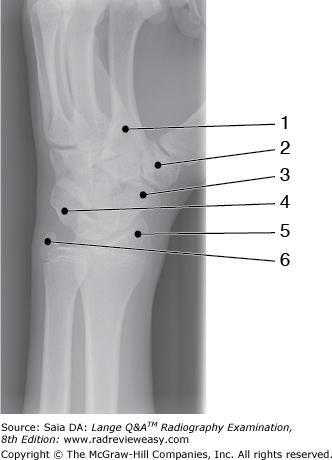

Which of the labeled bones in Figure A identifies the tarsal navicular?

Number 6

Which of the labeled bones in Figure 6–14 identifies the tarsal navicular?

What does the number 8 in Figure 6–14 identify?

Medial malleolus

Figure A was made in which of the following positions?

Lateral oblique